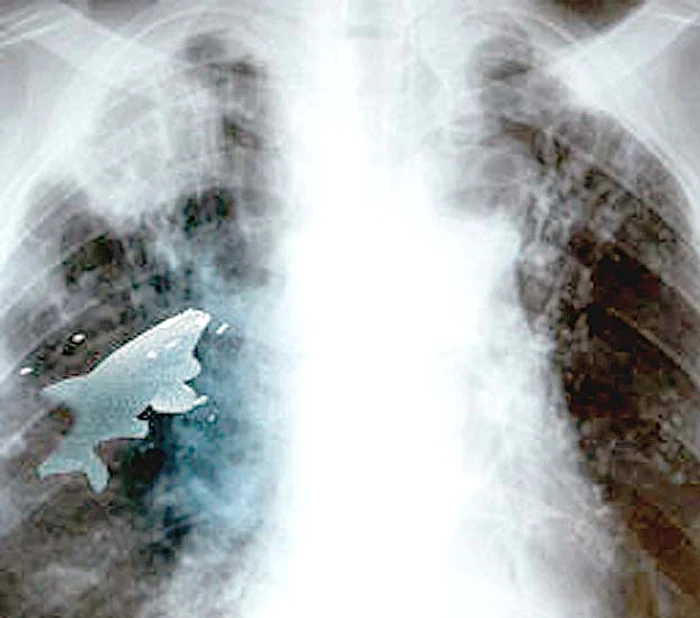

Şoc! I-au scos un peşte viu din plămân

Incredibil! Anil Barela, un băiat de 12 ani din India, a fost la un pas de moarte după ce a înfulecat un peşte viu. Peştele i-a scăpat pe trahee, în loc de esofag, şi i-a ajuns în plămânul stâng, împiedicându-l să mai respire.

Peştele măsura 9 cm şi nu a supravieţuit operaţiei

Anil a vrut să le arate amicilor că poate înghiţi dintr-o răsuflare un peşte viu cu lungimea de 9 centimetri. Numai că vietatea s-a zbătut şi i-a pătruns în căile respiratorii, oprindu-se în plămân.Copilul a început în scurt timp să nu mai respire bine şi a fost dus de urgenţă la spital.

La, radiografie s-a descoperit că peştele era viu, dar între timp a murit. Timp de 45 de minute, doctorul Pramod Jhawar l-a operat pe Anil şi a reuşit să scoată peştele înainte de a distruge plămânul. "Aşa ceva nu am întâlnit niciodată", a spus medicul, care are o carieră de 20 de ani.